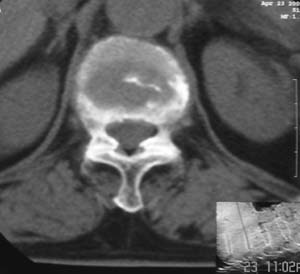

患者,女,72岁,胸背部疼痛3月余,无明显外伤史。曾应用局部封闭、非甾体类止痛药治疗效果不明显,近来疼痛缓解频感背困,平卧缓解,近日行ct检查发现胸12椎体病变,烦请同道发表意见,诊断什么?有何治疗经验!谢谢!!!

标绘图示:第十二胸椎级第一腰椎椎体楔形改变。ct扫描示:第十二胸椎椎体骨质结构紊乱,并可见一囊状低密度影,边缘可见硬化,椎体皮质完整。

考虑:第十二胸椎陈旧性骨折、许莫氏结节。